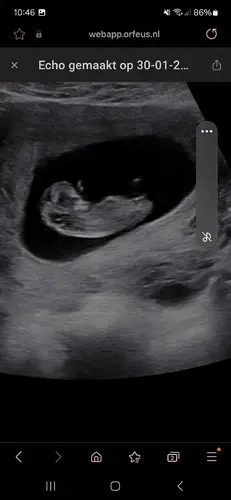

Iemand een idee? Verloskundige was 80% zeker.🙈

Meisje 🩷

Meisje!